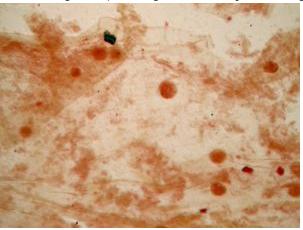

Slide có chứa máu mổ ruột muỗi khi R. Ross nghiên cứu